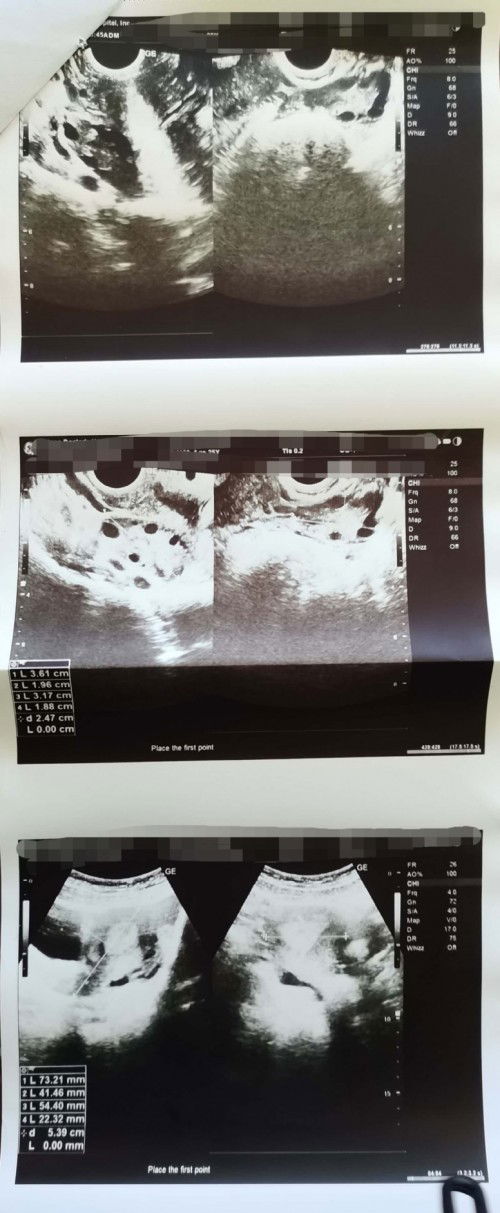

Ang counting ba talaga ng days ng pagbubuntis ay simula nung first day ng last menstruation mo? Paano naman kung irregular ang mens po (like me na may PCOS) April 15, 2022 pa kasi last menstruation ko. Tapos nagpa TVS&Papsmear Check up ako last May 25, 2022 pero before nun May 18 nag PT na ako (1 try lang) negative naman Tapos June 13, 2022 nalaman ko na buntis ako kasi nag PT ako 2 times at positive na.. At June 25, 2022 nag punta na ako sa OB at nag pa TVSultrasound nadin (8weeks na daw baby ko) #PCOSMom #PCOS #1stimemom #advicepls #